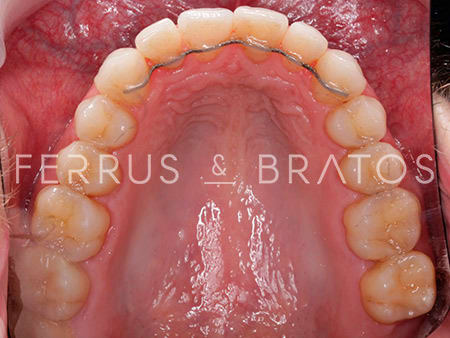

Raúl presentaba diversos problemas relacionados con su mandíbula: apiñamiento severo, una sobremordida muy aumetada y una ligera clase II dentaria. Cuando acudió a nuestra clínica, la doctora Patricia Bratos planificó un tratamiento con ortodoncia de brackets de Zafiro, un sistema muy estético y eficaz.

Una vez que corregida la alineación, la nivelación y la oclusión, la ortodoncista pautó un tratamiento estético para obtener un resultado aún más óptimo y natural. Dado que Raúl tenía tinciones en algunas piezas, la doctora recomendó un blanqueamiento tanto interno como externo para unificar el tono de la sonrisa. Ahora, Raúl nos cuenta que sonríe mucho más y con mayor confianza en sí mismo.